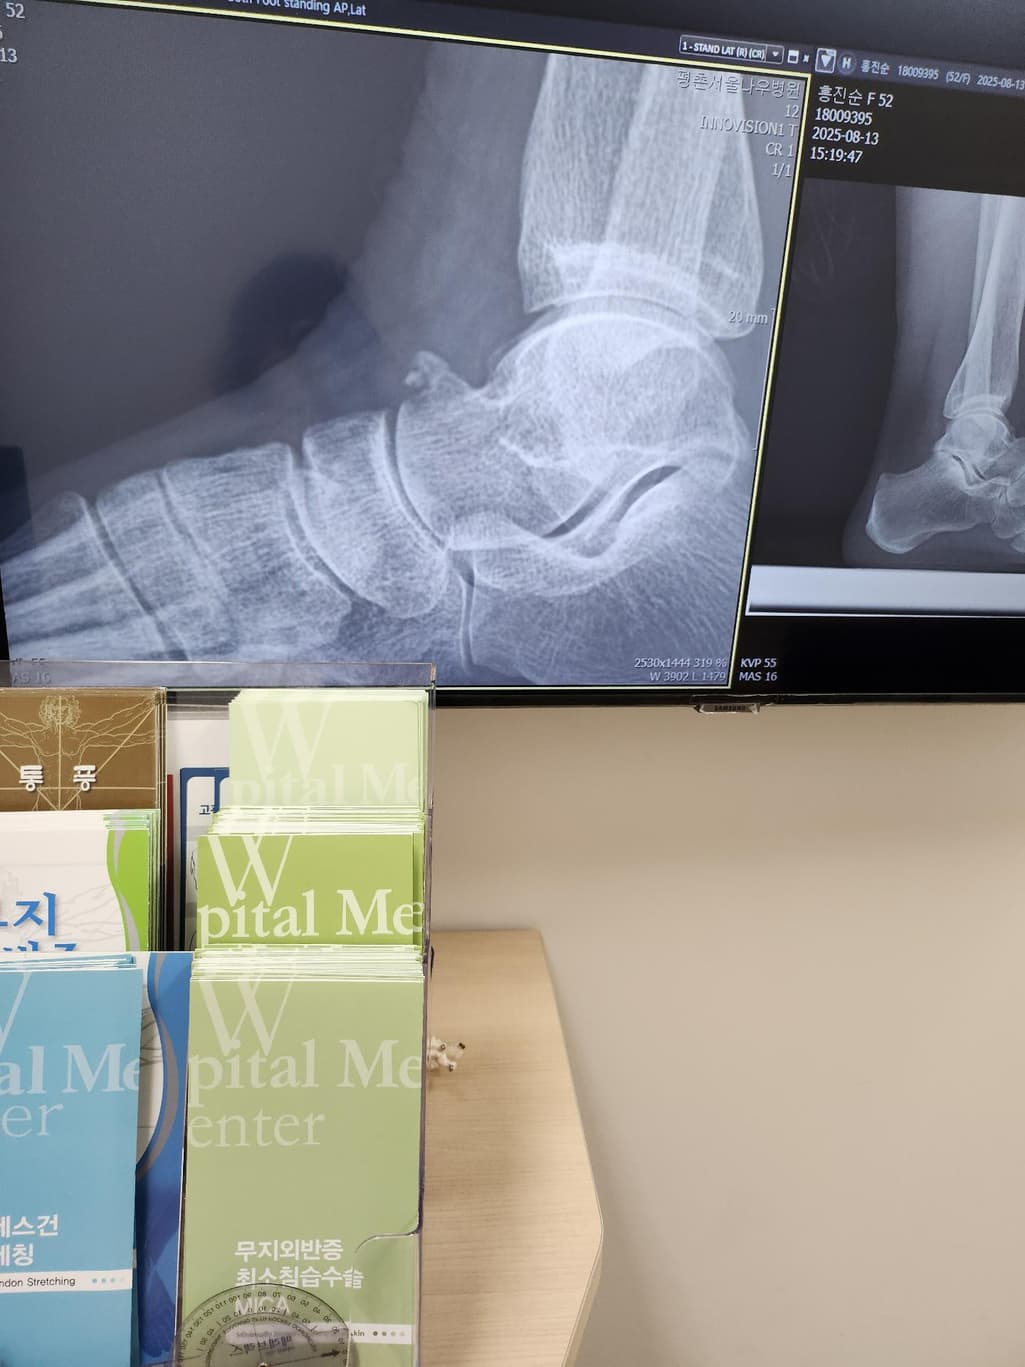

엑스레이와 ct촬영했는데요. 한번 봐주실수있나요?

선생님이 조각난 뼈가 자란건지 석회가 자란건지 모르겠다고 하셔서요 이런경우 정확히 알려면 어디 과를 가봐서 어떤검사를 더해봐야 할까요? 발등에 붙어있는게 아니고 떨어져서 있는데1년전보다 더 자랐다고 그래서 특정자세를 했을때 자극이 되니 통증이 있는것같아요

사진만으로는 조각난 뼈인지 석회성 변화인지 확정하기는 어렵습니다 정형외과 중에서도 족부 전문 진료가 가능한 곳에서 진료를 보는 것이 좋습니다 필요하면 mri나 ct 정밀 촬영으로 뼈와 주변 연부조직 상태를 함께 확인합니다. 통증이 반복된다면 단순 관찰보다 원인에 맞는 제거 치료 방안을 상담하는 것이 안전합니다!

더 자랐다는것은 우선 석회화 또는 골극의 가능성이 있지만 사진만으로는 판단이 어렵기에 전문의에 검사 및 진찰을 통해 확인 해주시길 바랍니다.